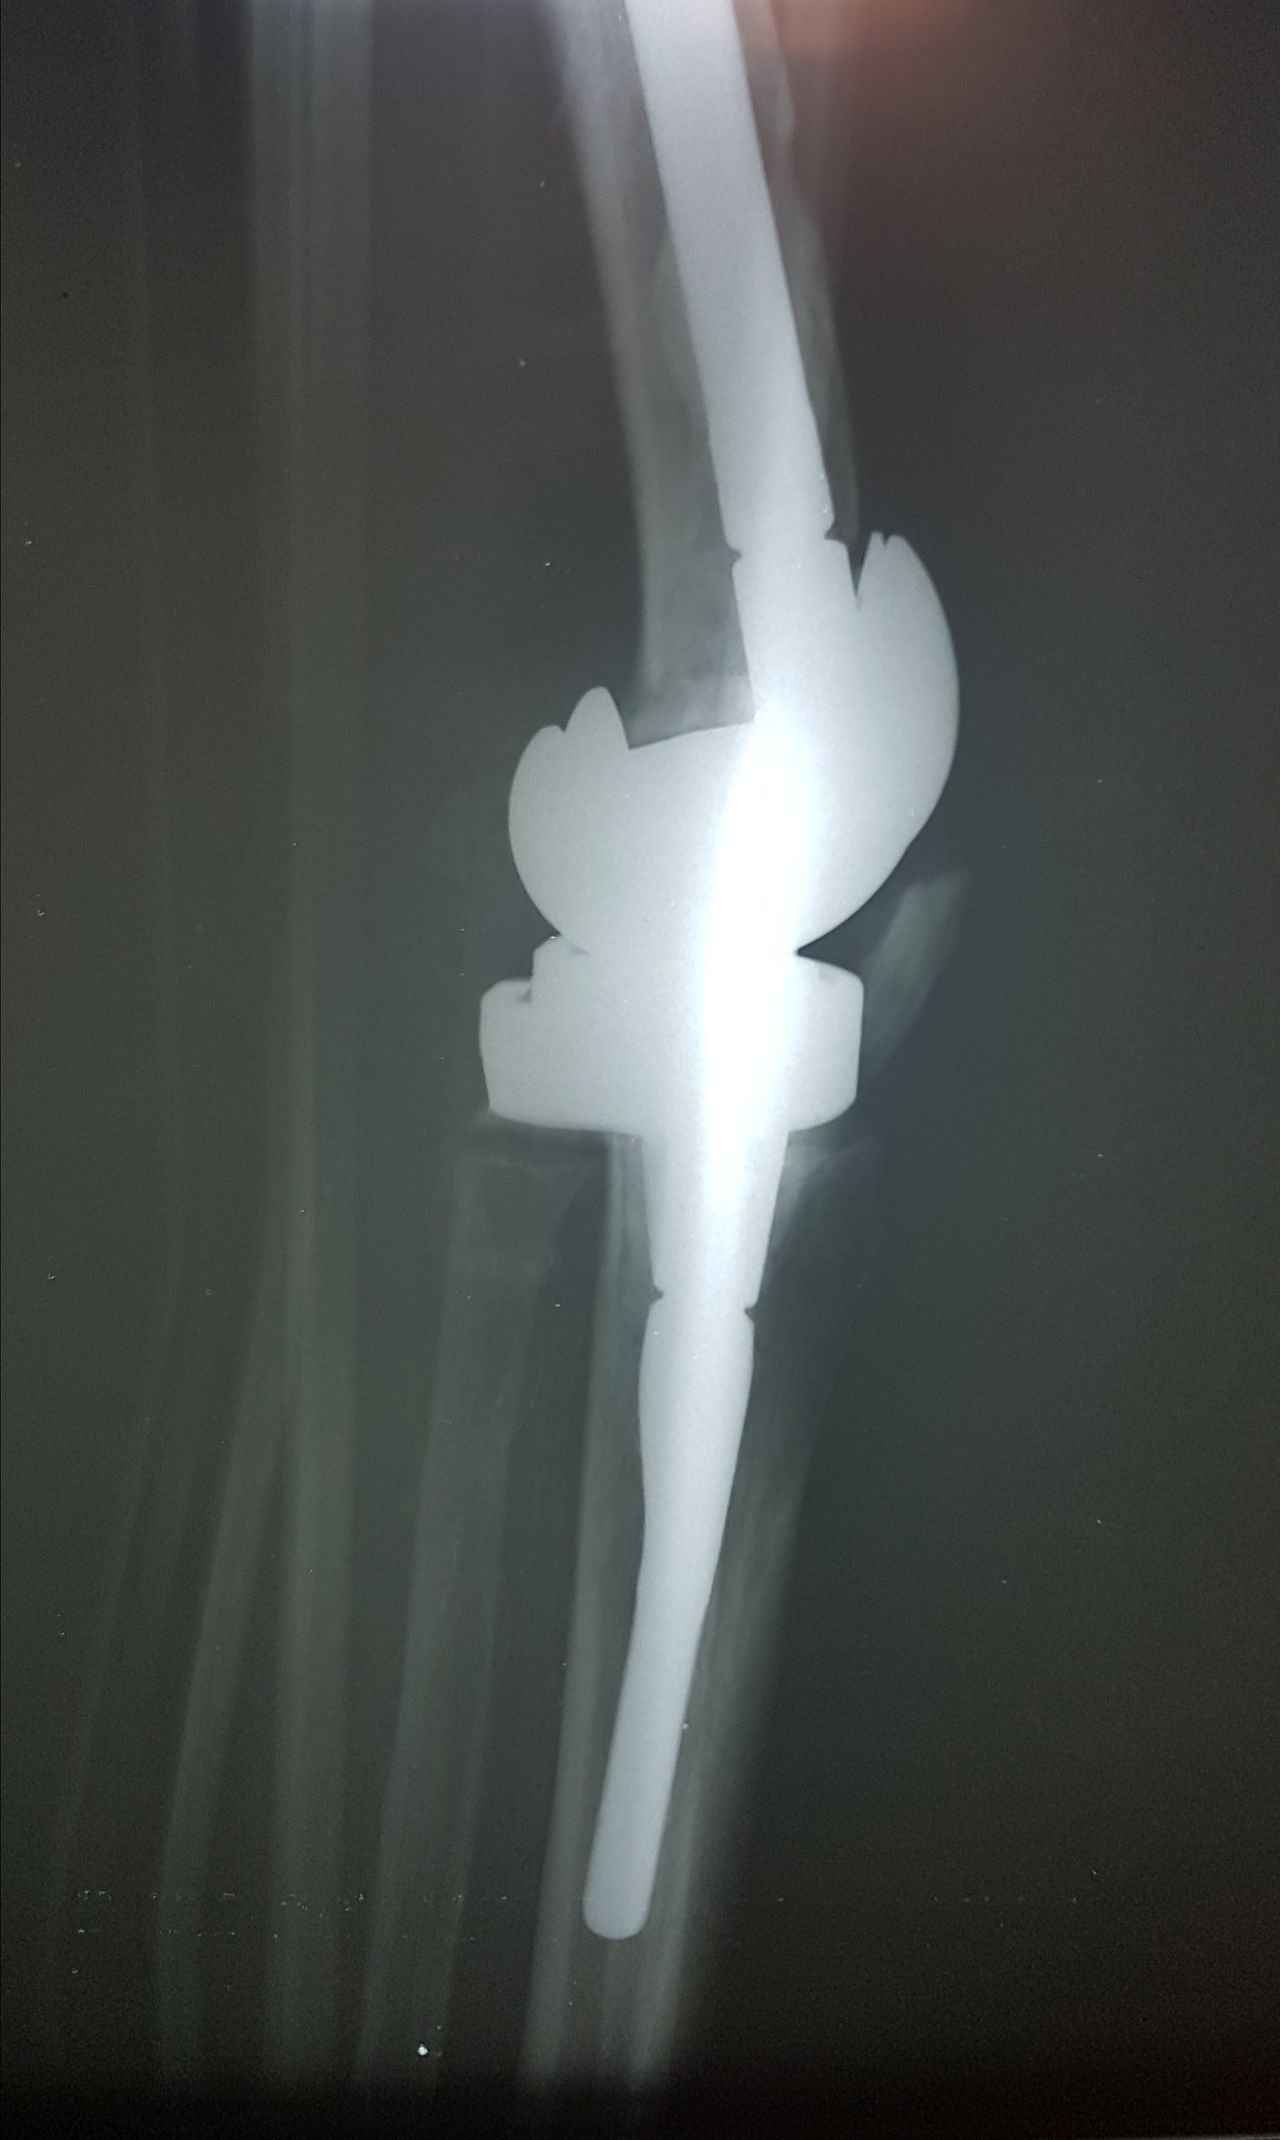

Soy   egresado  de  la  Universidad Autonoma de   Nuevo  Leon. especialidad de ortopedia y traumatologia  en    hospital  numero  21  del  IMSS ne Monterrey  N.L ,con entrenamiento en la  subespecialidad  de   reconstrucion  articular  y  artroscopia  que incluye  lesiones  de  meniscos  , reconstruccion de ligamentos cruzados , lesiones  condrales ,  gonartrosis   tengo  una  historia laboral    institucional de 30  años    hasta el 30  de lulio del 2024 estuve  10  años  en  el  modulo  de  artroscopia  con aproximadamente   1120    artroscopias  de rodilla   y  15 años  en  el  departamento  de    artroplastia  de rodilla  o  de  reemplazos  articulares   ,  los  ultimos   15  años    como profesor  adjunto   y titular  en los cursos    de pre  y posgrados  de  traumatologos  en la  subespecialidad  de  con aproximadamente   160 cirugias  institucionales    en   artroplastia de  rodilla    por  cada año   y  un  numero menor en el  medio particular  dando un total  aproximado  de  2,560  cirugias . de  estas  el  10%    de  revision  y  5%  preotesis    tumorales    de  actualmente   en  funciones  en  el  medio privado  y  acreditado  en todos los  hospitales  de la  localidad  y  con todas  las  aseguradoras   de  gastos  medicos .